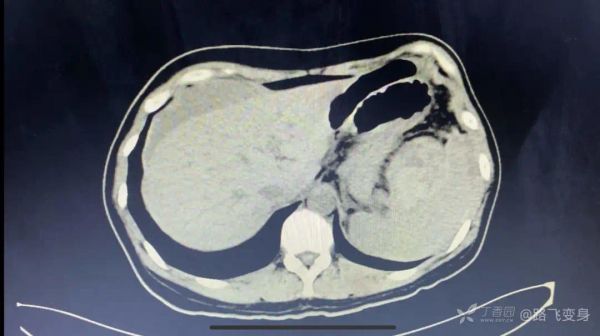

病人出现「休克」症状,没有办法只有准备手术,术前常规行全腹部 CT 检查,如下:

CT 发现明显异常。可以和下面第一次急诊 CT 视频做对比。

丁香园站友 @旧故里草木生 认为:两张片子对比,最明显的改变是脾脏周围有异常混杂密度影,肝周积液,又是个育龄期女性,大胆猜测脾脏异位妊娠导致的破裂。

丁香园站友 @zhangzihua87 认为:腹腔出血伴休克是没有疑问的。第一次 CT 脾门附近可疑软组织密度,第二次 CT 肝周积液,脾门软组织密度增大、不均,考虑破裂。一般考虑脾门血管瘤破裂。与妇科手术有关的话,大胆推测子宫内膜异位破裂。